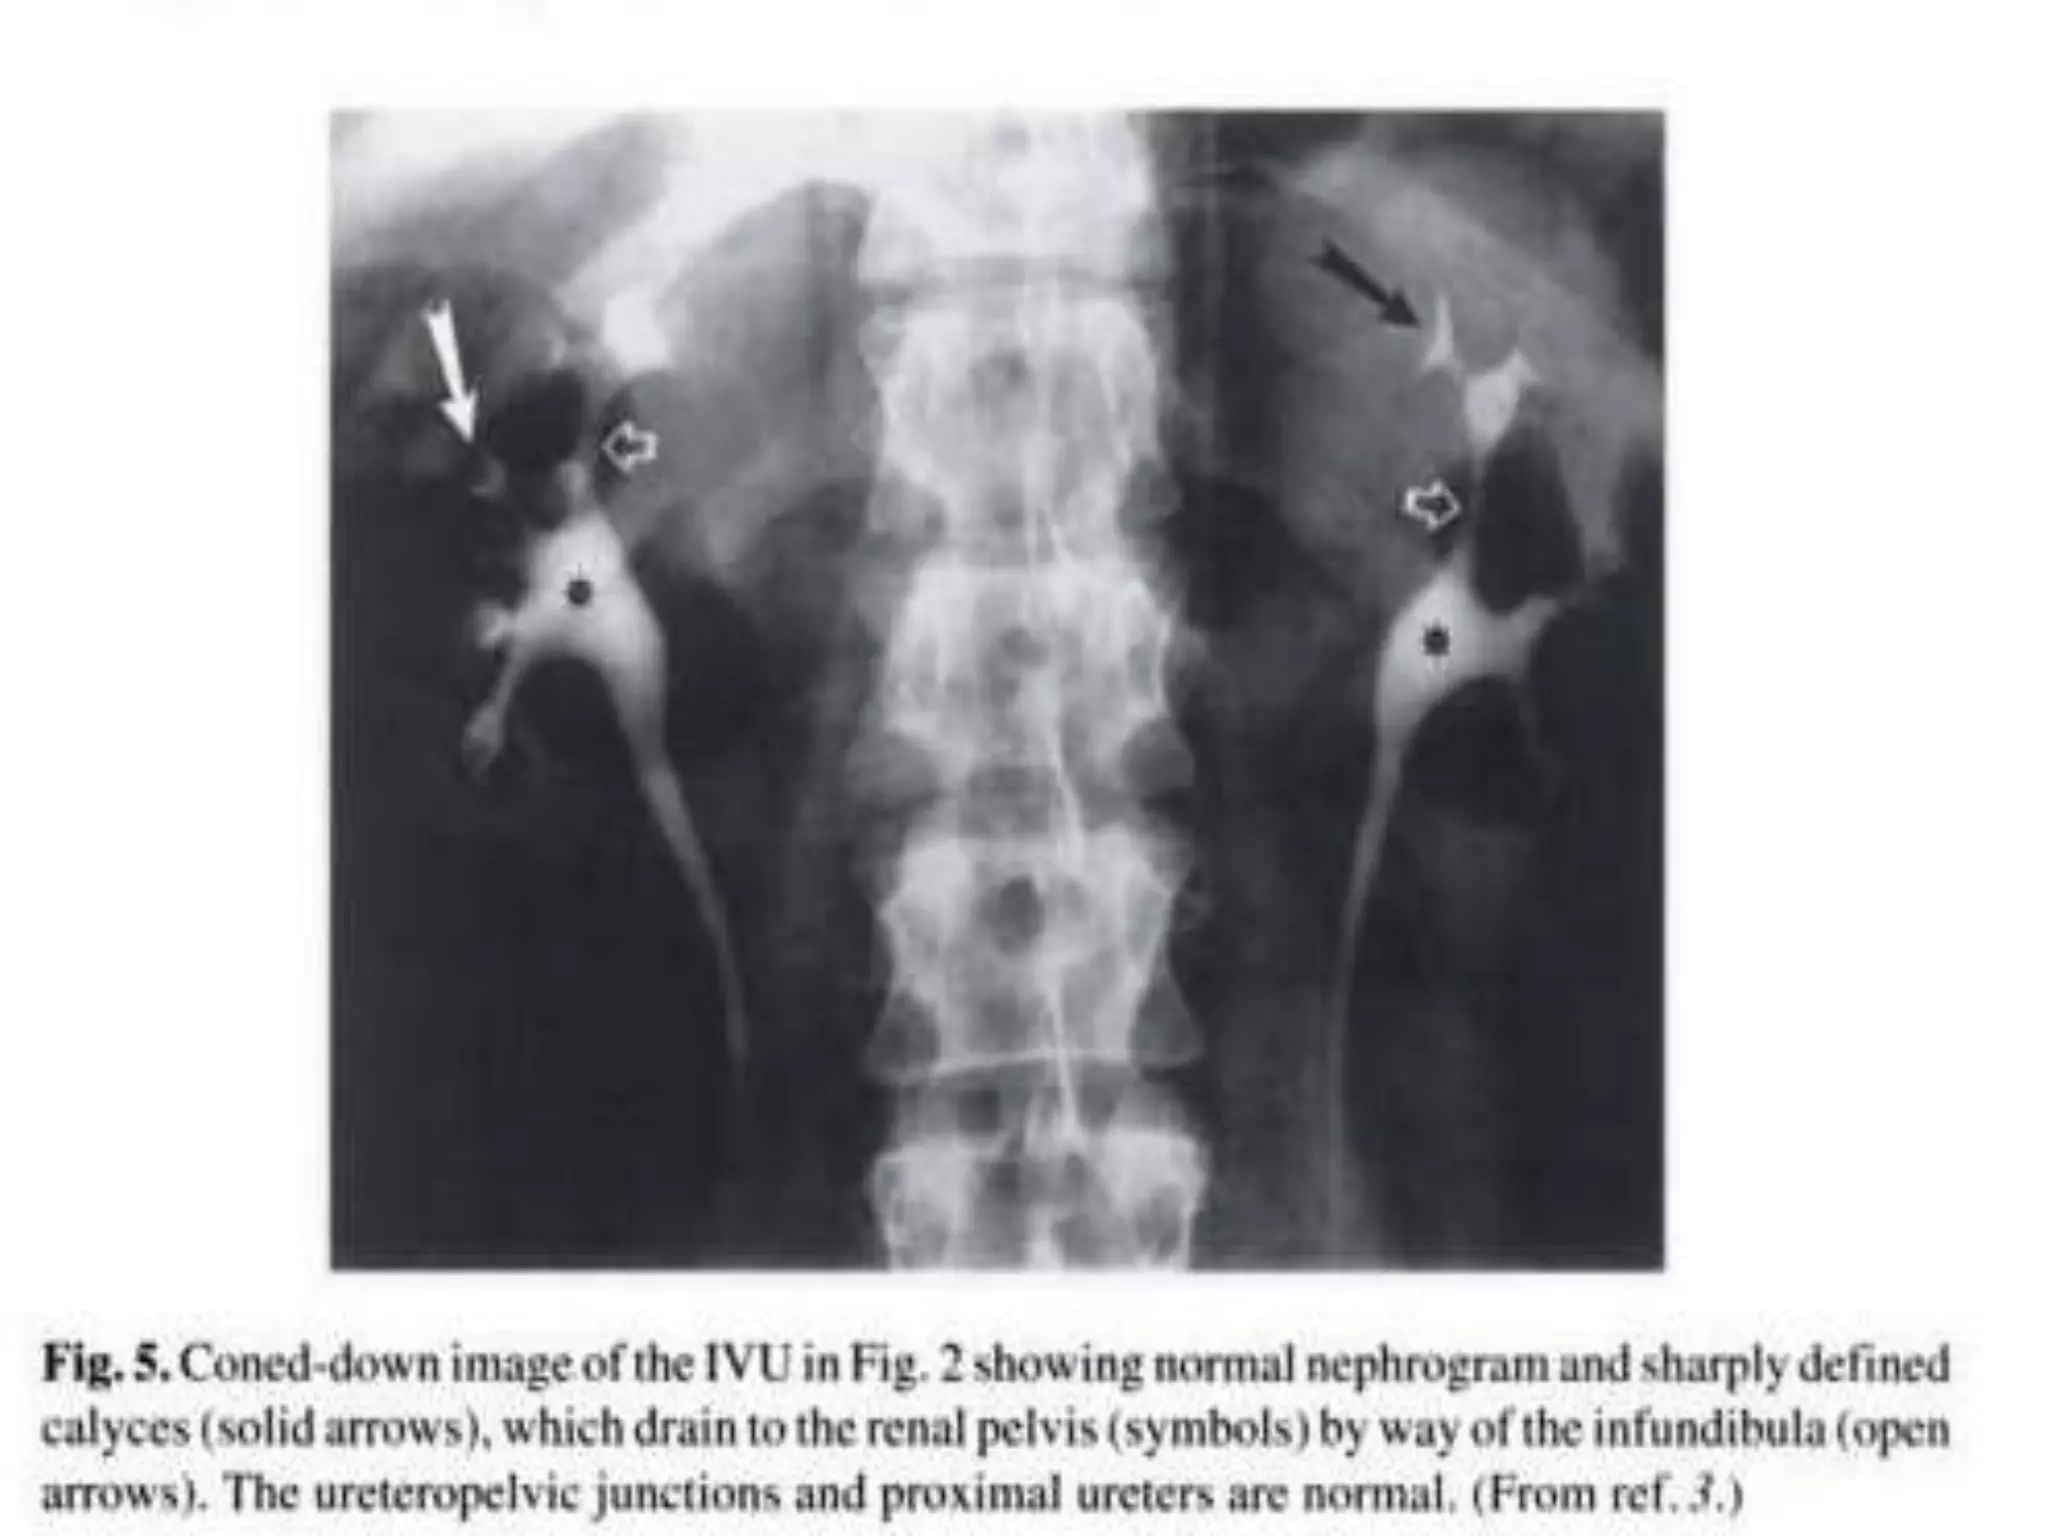

End of Injection, A.P. of the renal areas to show the nephrogram, i.e. the

renal parenchyma opacified by the contrast medium in the renal tubules.

Value of fluoroscopy. Fluoroscopic spot images demonstrate the entire

luminal surface of the ureters.